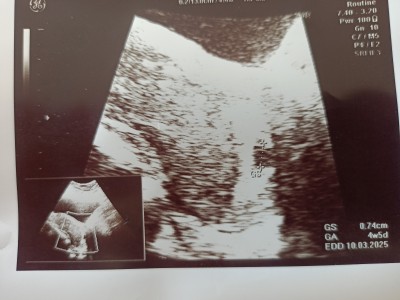

hicbirsey anlamadım kese nerede şimdi

Bebek yada kese nerede

İki + işareti var bak ultrasyon kagdinda

Gebelik kesesi

İki işaret var orda o kese işte